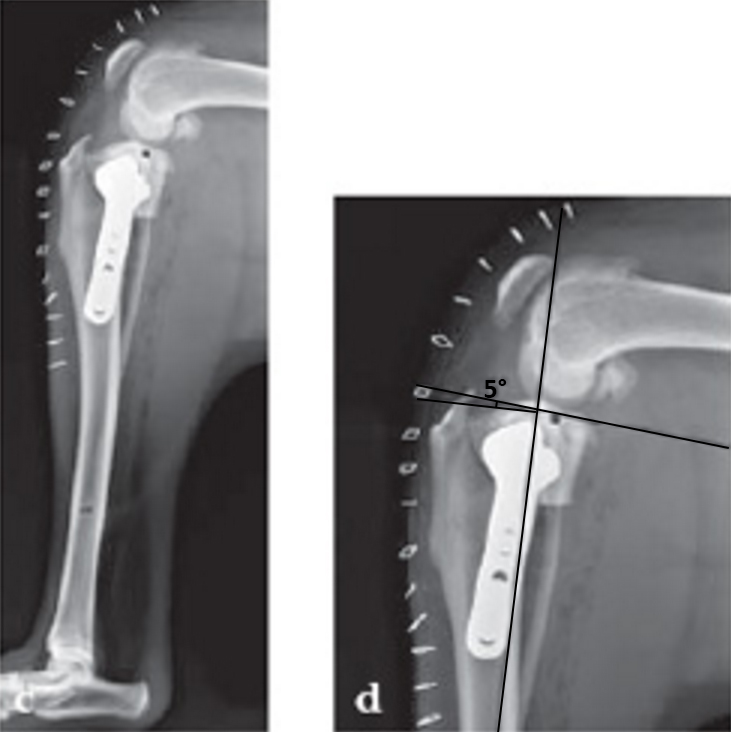

Case 4: Three-year-old neutered female Tosa, 60 kg, chronic (6 months) lameness, painful stifle.

(Case provided by Randy Boudrieau, North Grafton, USA)

Tibia plateau leveling osteotomy (TPLO) is a surgical procedure developed for the treatment of cranial cruciate ligament deficient stifles in dogs. TPLO is proposed to decrease cranial tibial thrust by controlled rotation of the tibial plateau. Currently, conventional and angular stable plate fixation can be performed to stabilize the cylindrical osteotomy. This study investigated the biomechanical consequences of the procedure including the effect of using either conventional or locking head screws in the tibial plateau fragment.

Eight pairs of cadaveric dog tibiae were instrumented with titanium reference pins in order to track the tibial plateau fragment orientation by means of CT imaging. Position of the tibial plateau was determined for the intact bone, after rotation of the fragment, and after plate application (Fig 1). Bones were pairwise instrumented by an experienced surgeon with TPLO plates using either conventional or locking head screws in the tibial plateau fragment. All specimens were biomechanically tested in physiological orientation using cyclic axial compression at 1000 N for 30.000 cycles. Stiffness at the beginning of the test and plastic deformation of the construct at the end of the test were determined in terms of displacement of the machine actuator.

The conventional screw group revealed a significant larger translation of the fragment towards the plate (P =.006) and a greater variance

in fragment rotation as a result of plate application (Fig 2). However, maximum deviations of the achieved tibial plateau orientation from the preoperatively planned orientation were up to 5 for both groups. The amount of this rotation correlated significantly with the plastic deformation of the construct after testing in the conventional screw group (R = 0.81, P = .005). Neither plastic deformation nor construct stiffness were significantly different between conventional and angular stable plate fixation.

This study demonstrated less variation of the tibial plateau position due to instrumentation with an angular stable TPLO plate. However, the fixation type did not affect the biomechanical stability of the construct. Within the conventional group a higher biomechanical stability can be achieved due to a lower degree of rotation which leads to a larger bony contact between the fragments.